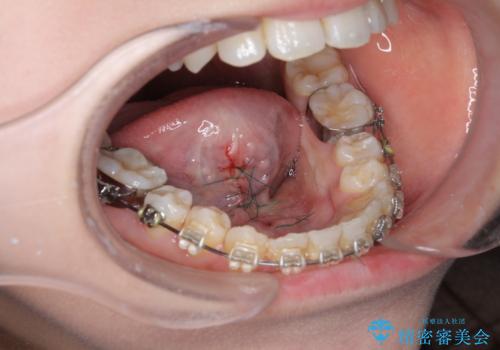

滑舌を改善! 舌小帯の形成術

- 他院での矯正治療中、滑舌の改善を求めて来院されました。

10分程度の短時間で終わる、舌小帯の形成術を行い滑舌の改善を計画します。

術後すぐに、ら行さ行の発音がしやすくなった!と喜んでいただくことができました。